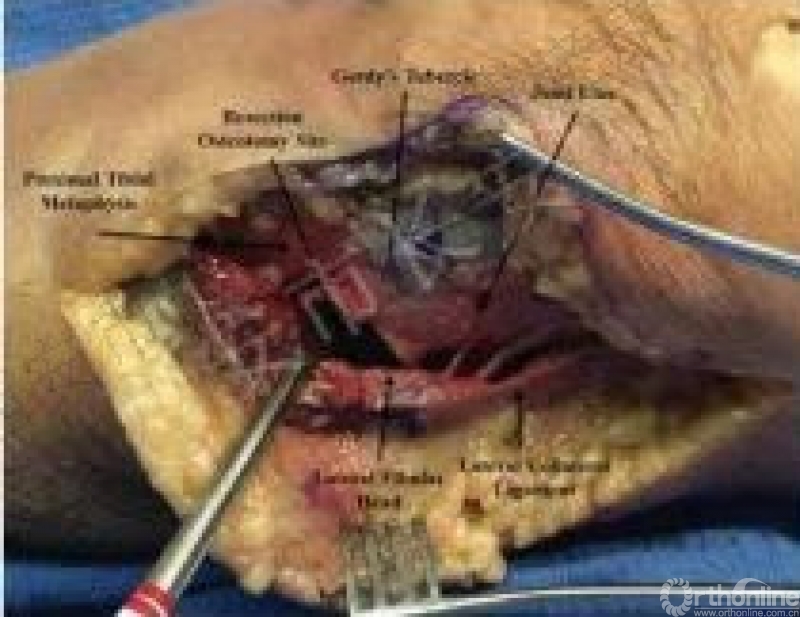

原文:采用标准的前外侧入路,但皮肤和筋膜切口向后移,在Gerdy结节和腓骨头之间分开。